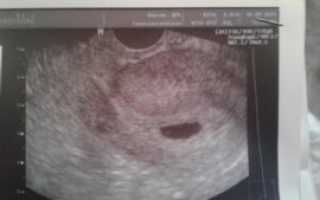

В этот же период начинается рост плаценты – уникального органа, обеспечивающего защиту и питание плода. Из трофобласта и эктодермы образуются амнион и хорион. Амниотическая полость заполняется околоплодными водами, а хорион начинает активно продуцировать ХГЧ. Размеры эмбриона достигают значения в 4 мм и его уже можно увидеть на УЗИ.

После проведения анализа на содержание в крови хорионического гонадотропина женщина уже может знать, что она носит в себе новую жизнь. Спустя 3 недели беременности, что происходит с плодом – можно разглядеть с помощью ультразвукового исследования.

На этом этапе эмбрион представляет собой крошечный шар с едва различимыми головным и хвостовым концами, окруженный плодным яйцом. УЗИ-диагностика на ранних сроках беременности проводится двумя способами:

Именно УЗИ на третьей неделе после введения эмбрионов является методом, позволяющим достоверно определить наличие беременности, так как ЭКО, к сожалению, не всегда может гарантировать удачный результат.

Кроме того с помощью ультразвукового сканирования можно увидеть:

• Количество жизнеспособных эмбрионов в матке;

• Место расположения плодного яйца;

• Изменения в яичниках.

Первое УЗИ является необычайно важным для исключения серьезных патологий в виде внематочной беременности, остановки развития плода, определения многоплодной беременности и необходимости дальнейшего проведения или коррекции поддерживающей терапии.